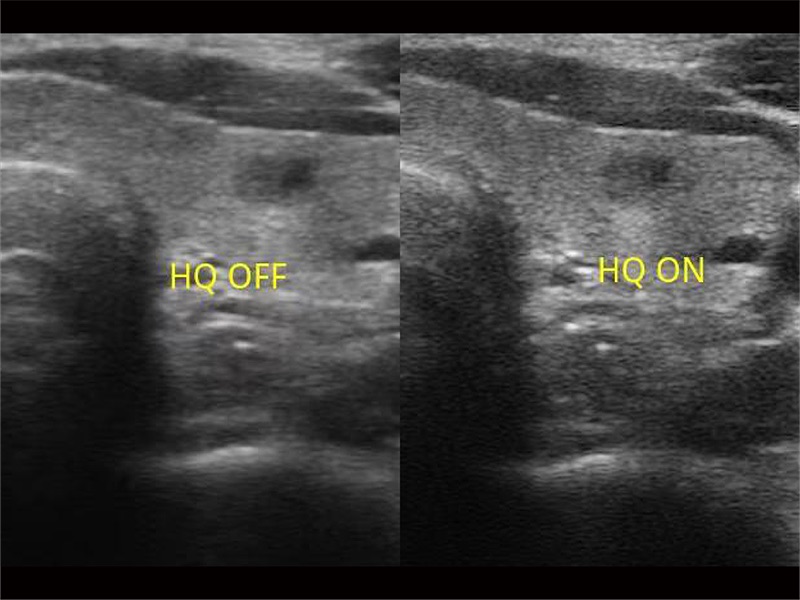

ProPet80 vereint die neueste intelligente veterinärmedizinische Software mit der Monokristall-Schallkopftechnologie, um außergewöhnliche Bilder zu liefern, die auch subtilste Veränderungen erkennen lassen - bei Doggen bis hin zu winzigen Exoten - und liefert deutlich bessere klinische Ergebnisse.